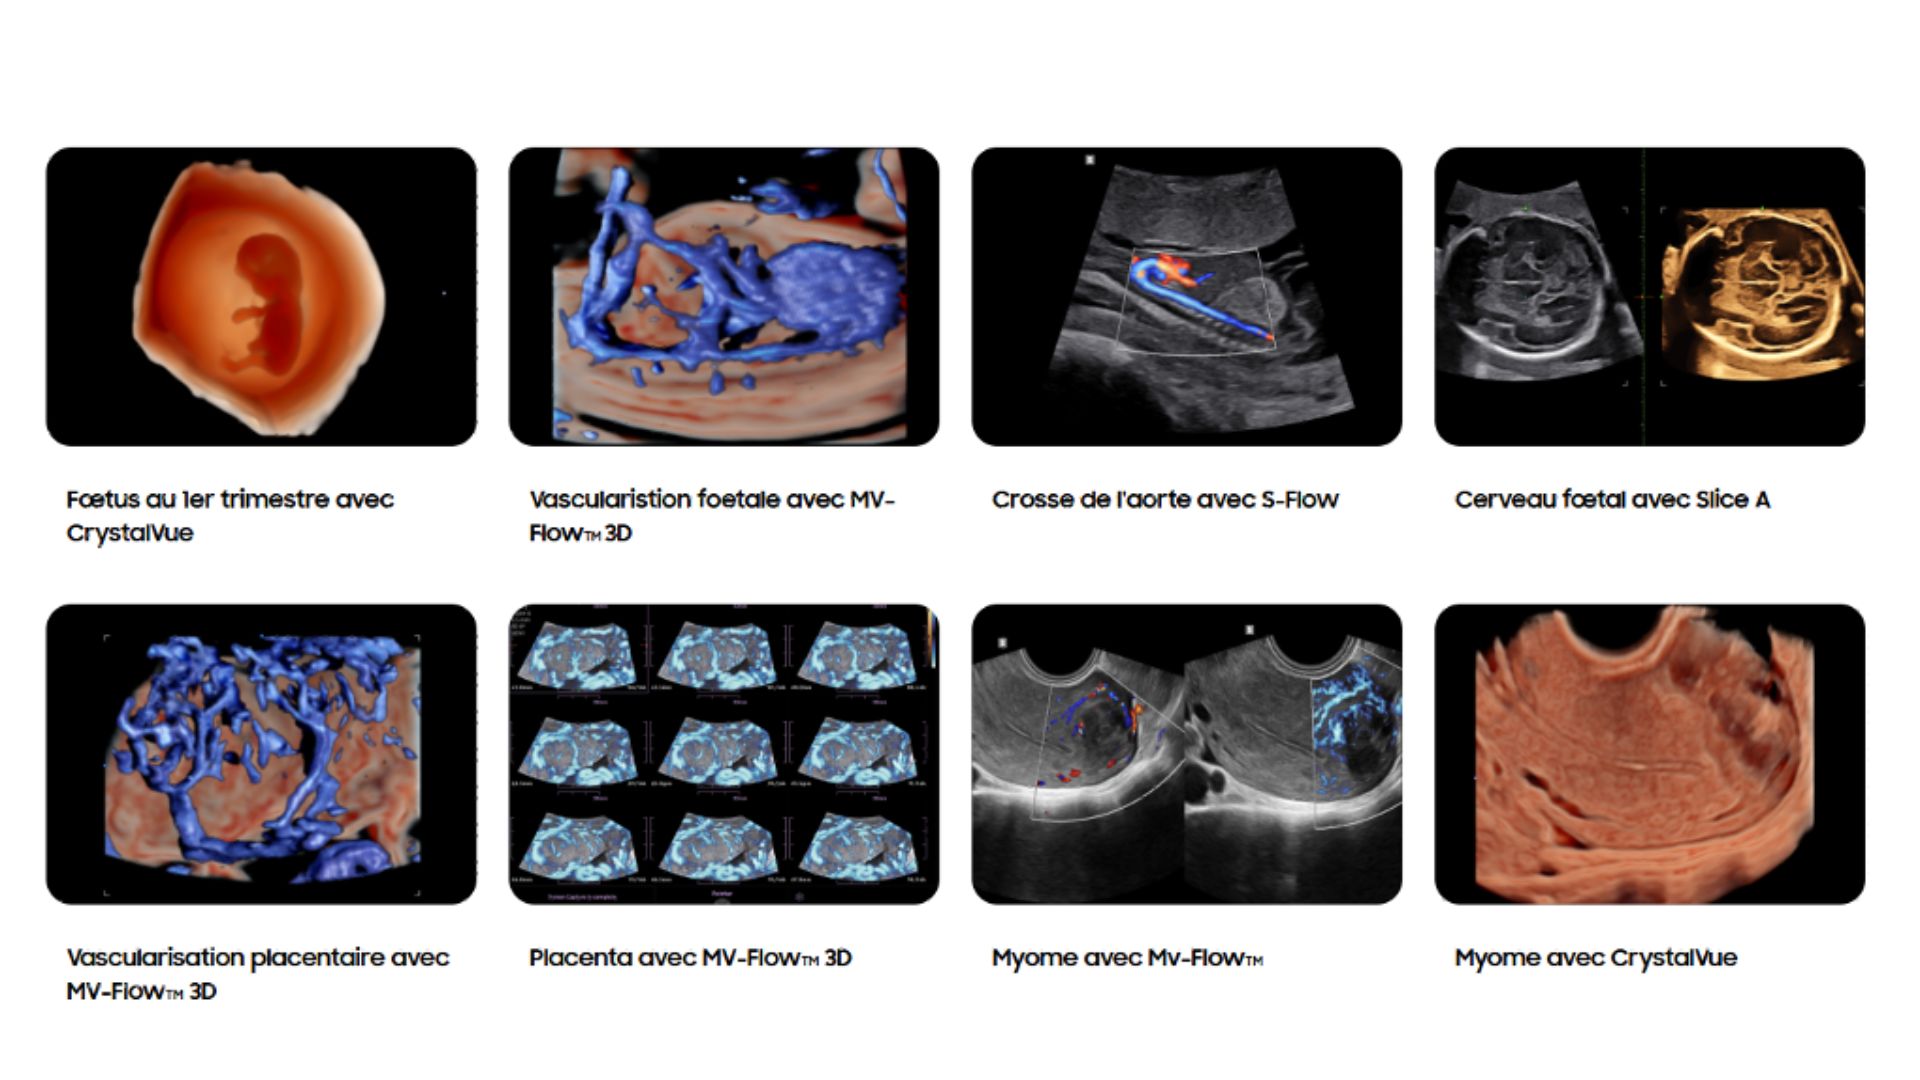

MV-Flow™ offre une nouvelle alternative au Doppler Énergie pour visualiser les flux lents et la microvascularisation des structures. Les hautes cadences images et les filtres d’imagerie avancés permettent au MV-Flow™ de coder le mouvement des hématies en s’abstenant des artefacts de l’imagerie B et ainsi améliorer la résolution spatiale.

LumiFlow™ est un codage de visualisation avec un effet tridimensionnel qui permet d’étudier l’architecture des vaisseaux, de manière intuitive.

RealisticVue™ affiche une anatomie 3D haute résolution et une perception réaliste de la profondeur. Une source lumineuse est modélisée afin de permettre un effet d’ombre sur les structures et de surligner les zones d’intérêt.

CrystalVue™ est une technologie avancée qui permet de visualiser sur un rendu volumique, les structures tissulaires et les structures osseuses. Ce mode utilise la superposition des différentes échogénicités afin de permettre la visualisation de toutes les structures sur un même volume.